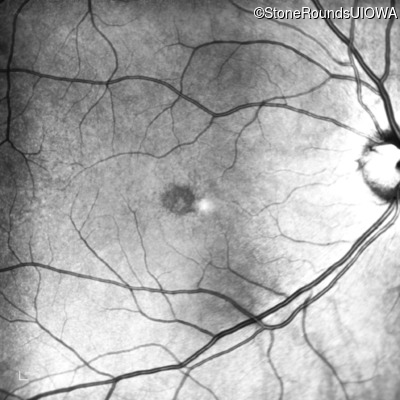

Infrared Fundus Photograph - Right - 20/20 -1

Exemplar